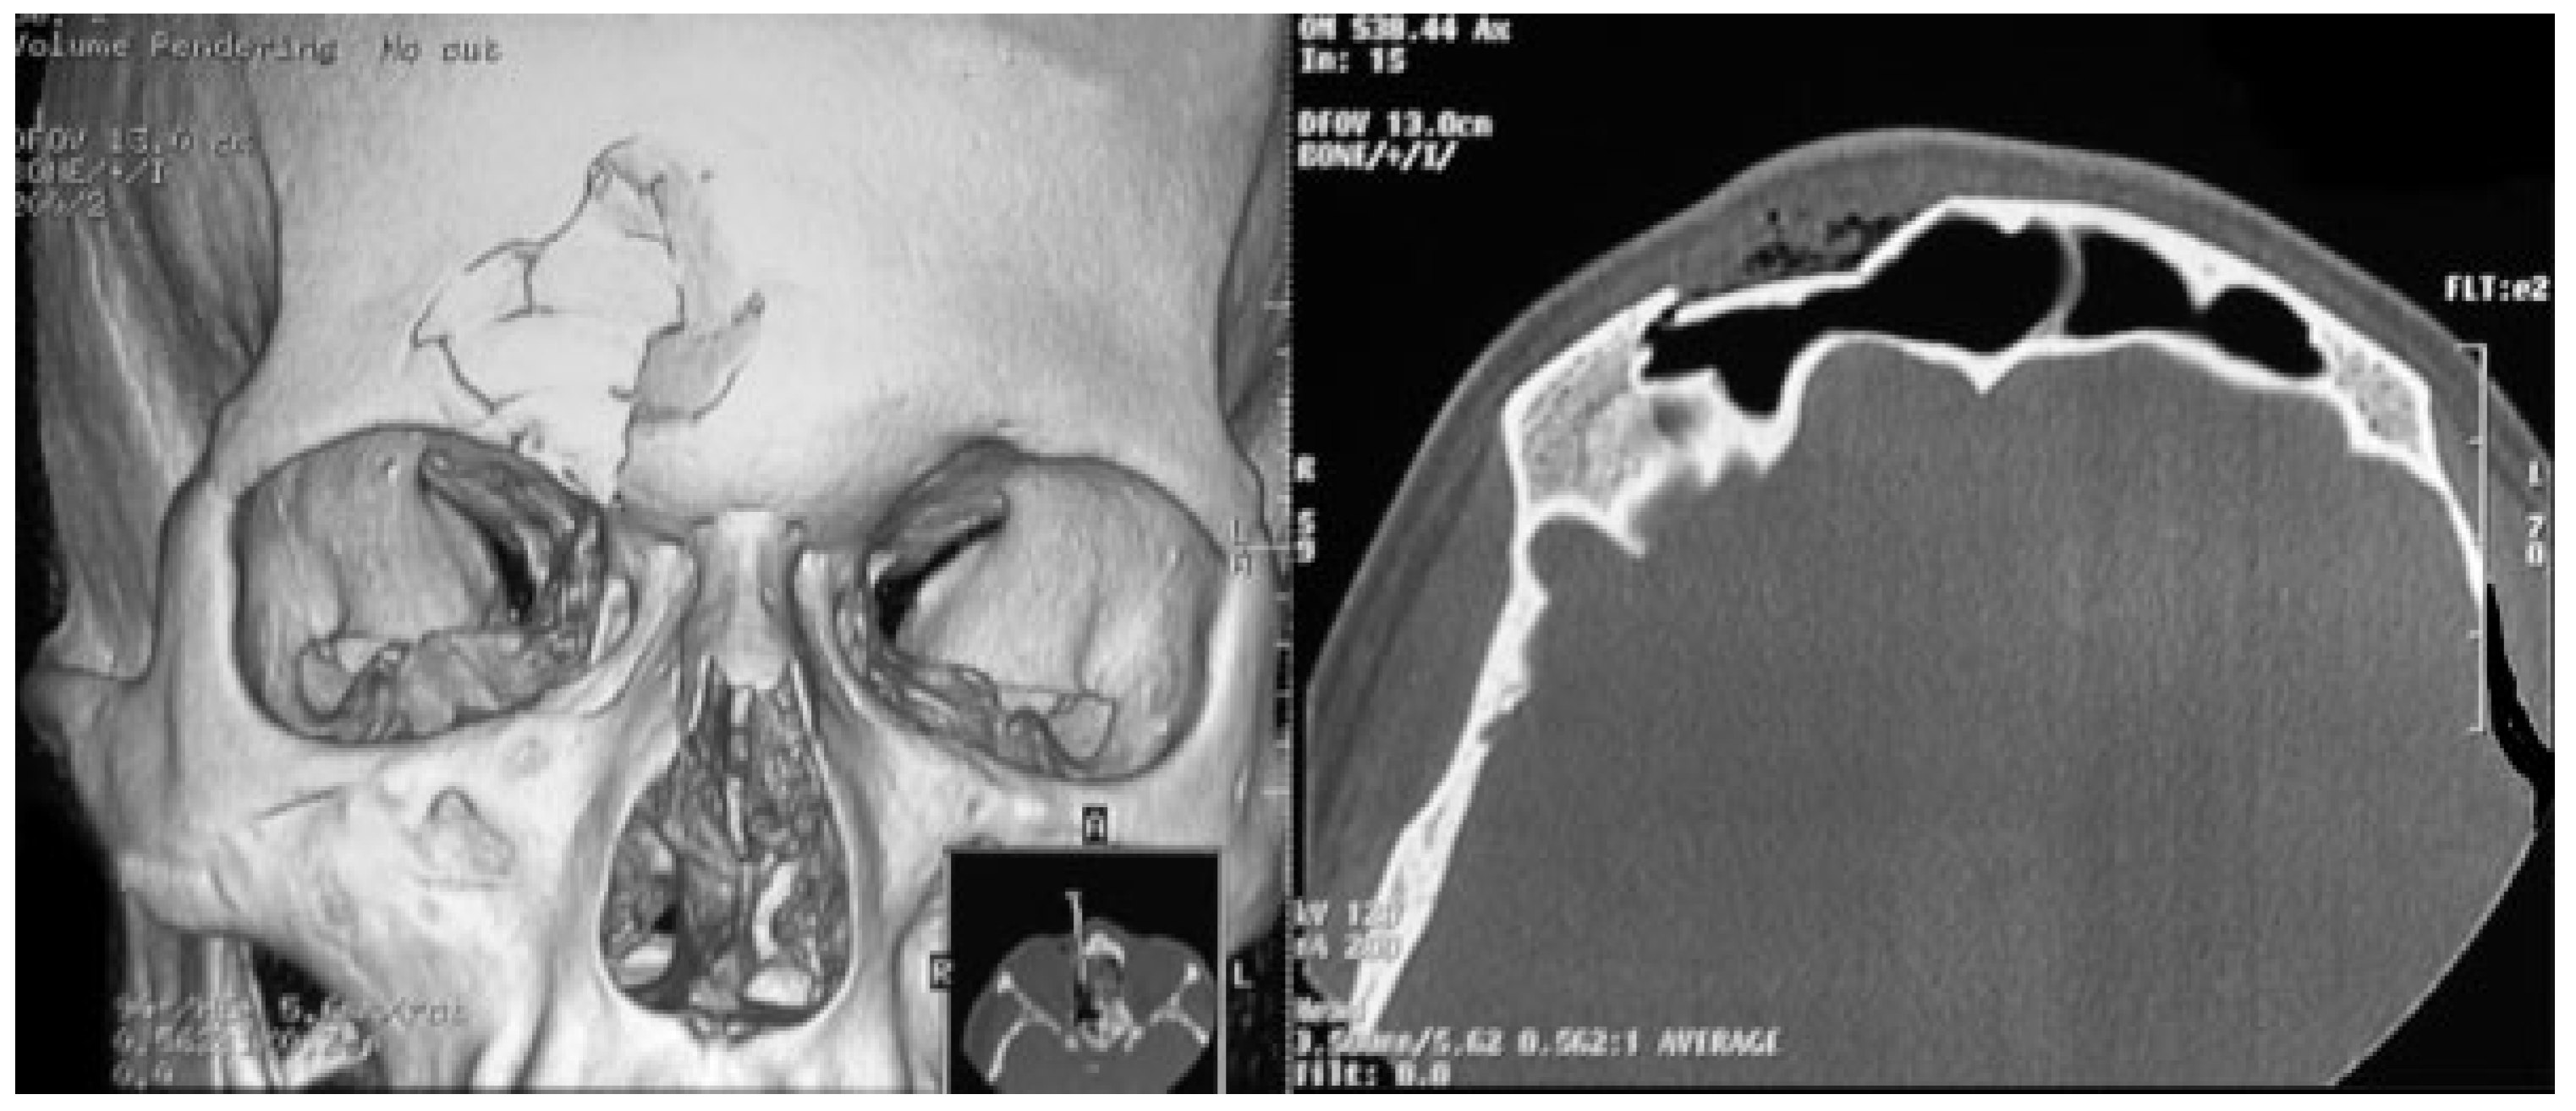

The BMPUT is also best performed via a coronal approach, which enables restoration of the ideal frontal bone profile without scarring in the frontal region. The esthetic outcome resembles the preoperative situation. The BMPUT also allows the use of all bone fragments, including small (<1.5 cm) fragments that are typically removed because they are difficult to synthesize with conventional plates and screws. Thus, the continuity of the frontal sinus wall can be reconstructed without a graft, reducing the surgical time. Healing is also improved, sinus sealing is avoided, and the incidence of infective complications and mucoceles is reduced. Probably, the resorption of bone fragments and loose of screws fixation could be prevented from this surgical technique (Figure 7).

Figure 7. Postoperative computed tomography with three-dimensional image.